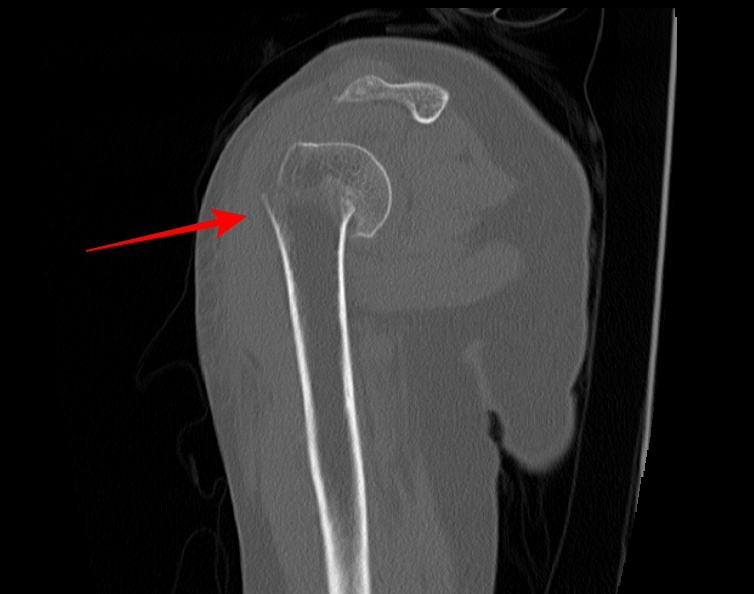

2022.06.04 CT SCAN

- F/50대

- 어제 넘어짐

-velpeau bandage 상태

- Rt Shoulder CT

- surgical neck Fx 의심 되어 검사 의뢰됨.

- 오른쪽 어깨에 velpeau bandage를 한 상태로 통증이 있는 상태였다.

- shoulder 전체를 포함하여 scan 하였다.

- axial 영상을 획득 후 MPR로 재구성하였다.

- 붉은색 화살표가 골절된 부위다.

displaced neck fracture of humerus with impaciton

입원 후 수술예정이다.